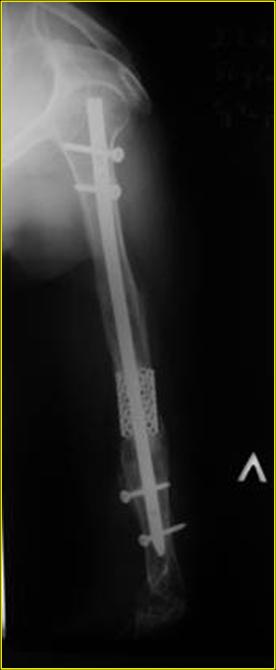

Типичная положительная ситуация для интрамедуллярного остеосинтеза с

использованием опорного металлокаркаса для компенсации дефекта.

Рентгеновская версия реконструкции. хронология:

после операции, 2 мес. после операции, через 1 год

Движения в полном объеме восстановлены к 2 мес. после операции. Если надо могу показать мультик. Сейчас уже прошло более 3 лет, больная не